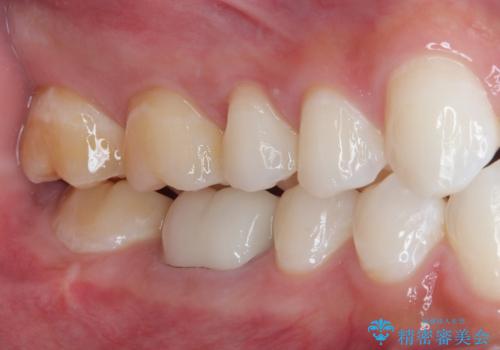

審美面、機能面共に満足していただけました。

舌側の虫歯が大きかったため歯茎の腫れが心配でしたが腫れもなく経過良好です。

引き続き矯正後の後戻りのチェックを行っていく予定です。